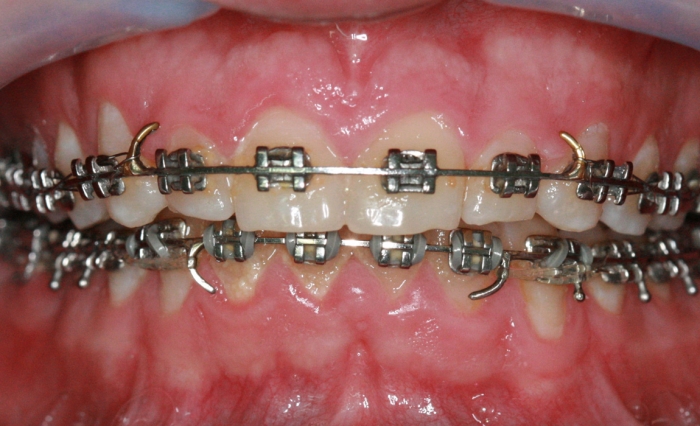

Mordida, após 2 anos da cirurgia